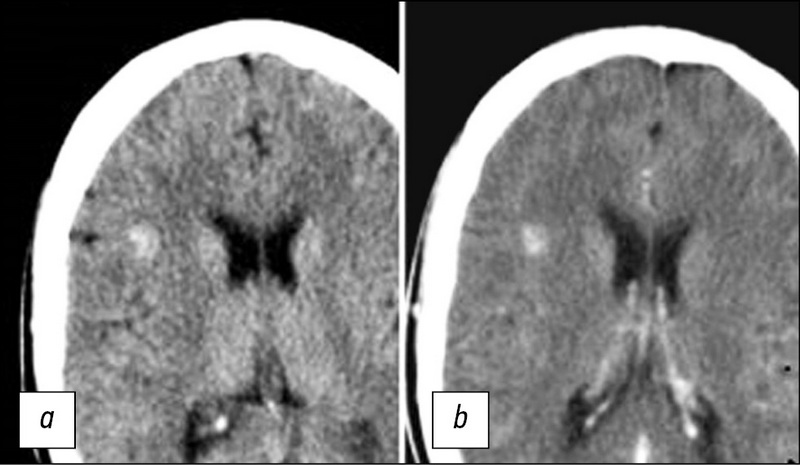

Лучевая диагностика кавернозных мальформаций головного мозга

Кавернозные мальформации головного мозга в настоящее время являются достаточно распространённой сосудистой патологией: число выявляемых случаев в последние годы резко возросло. Это связано с внедрением в клиническую практику и повсеместным распространением современных методов нейровизуализации, таких как компьютерная (КТ) и магнитно-резонансная (МРТ) томография. До появления КТ и МРТ диагностировать данную патологию было весьма трудно, и диагноз чаще всего устанавливался интраоперационно или по данным аутопсии. Обзор литературы посвящён лучевой диагностике кавернозных мальформаций (КМ) головного мозга. Проанализировано значение методов нейровизуализации для диагностики кавернозных мальформаций, а также применение МРТ для визуализации КМ. Выявлены преимущества МРТ перед другими методами нейровизуализации данной патологии. Охарактеризованы импульсные последовательности МРТ и сигнальные характеристики очагов различных типов в зависимости от морфологического субстрата. Проанализировано значение последовательности SWI (susceptibility weighted imaging) для обнаружения многоочаговых поражений в случаях семейных форм КМ. Изучение основных импульсных последовательностей МРТ для визуализации кавернозных мальформаций позволит оптимизировать алгоритм протокола для своевременной диагностики данной патологии и выбора тактики лечения.